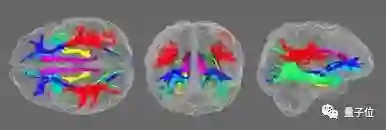

接着是DTI 数据采集分析

先了解一下DTI这个概念。DTI,又称弥散张量成像,用来描述大脑结构,可以说是核磁共振成像的特殊形式。

如果说,核磁共振成像是追踪水分子中的氢原子,那么弥散张量成像则是依据水分子移动方向来制图。

「弥散」二字,就指的是分子随机不规则的运动。

它一般应用于脑缺血、脑白质疏松、大脑发育成熟退化等临床应用。

而这个DTI采集到的数据,则通过一个叫做各向异性分数(FA)的数值,来定量描述脑白质中的结构功能。

简单来理解便是,FA数值越高,代表脑白质的功能更加完整、更加活跃。

而本次受试者共有1065位,他们均使用的是标准32通道西门子接收头线圈和一个 “身体 “传输线圈测量DTI。

就像这样。